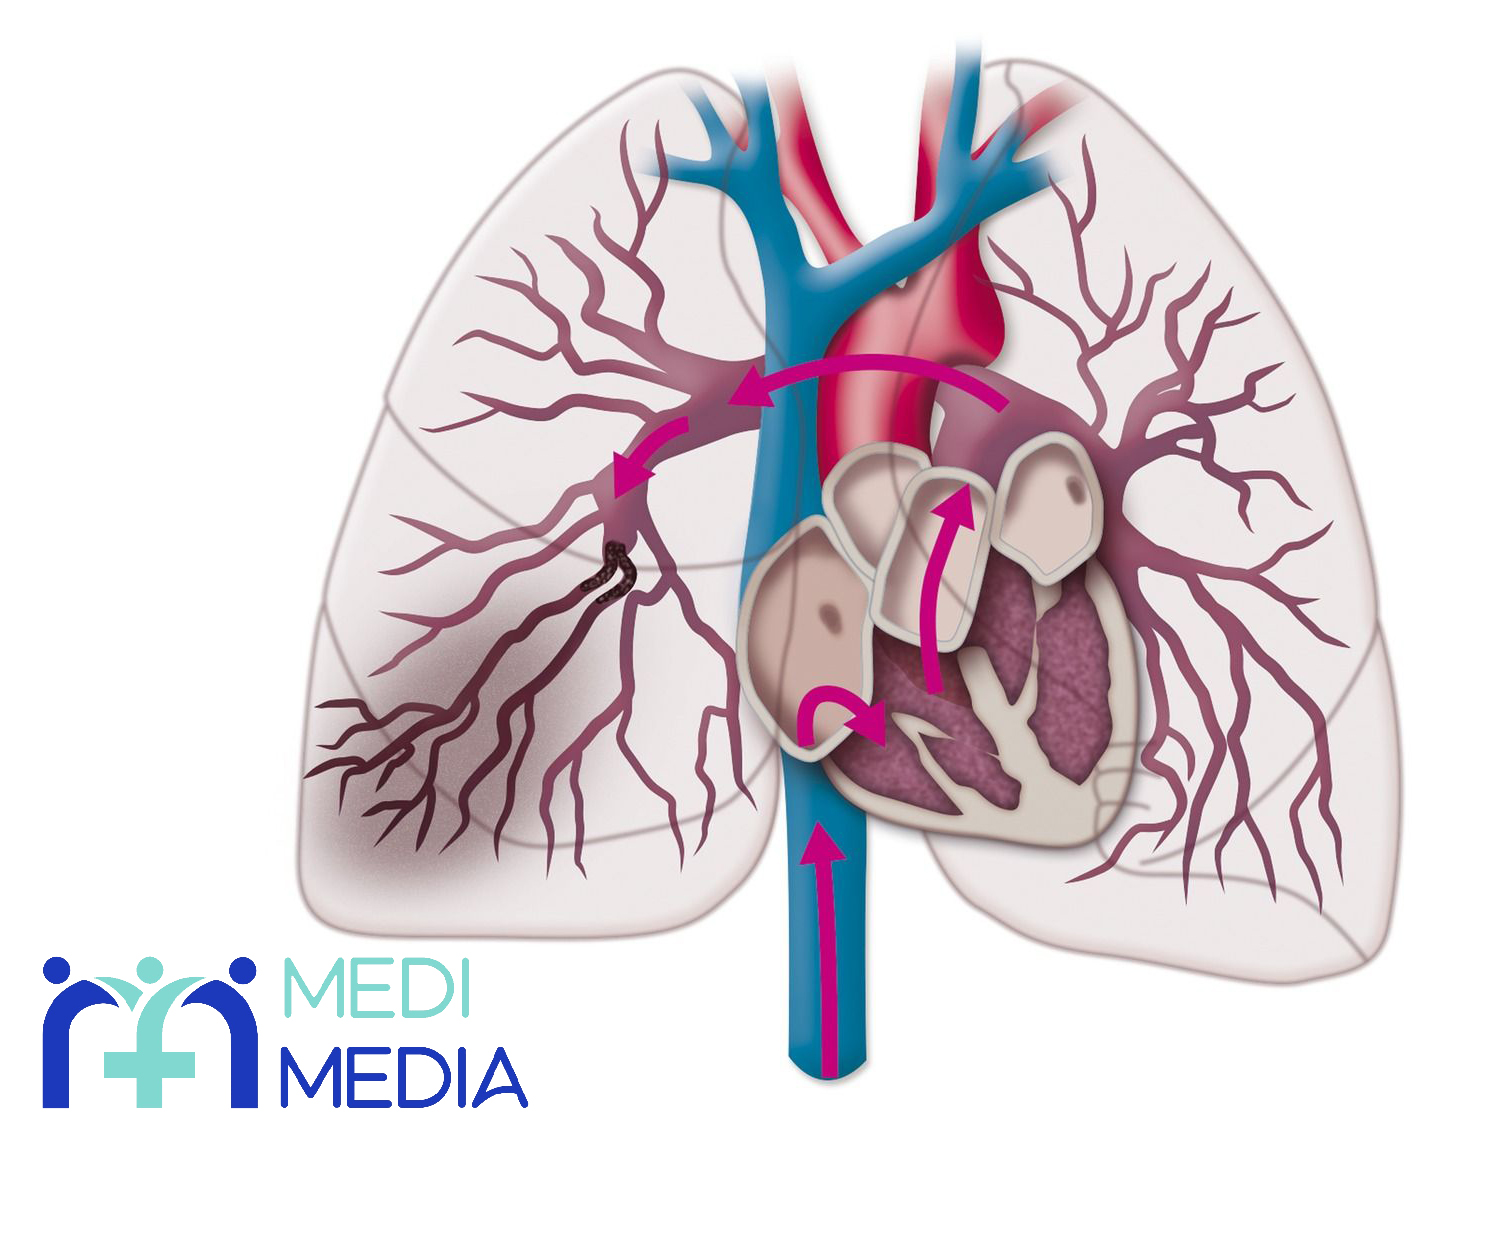

آمبولی ریوی بیماری است که در طی آن، در عروق خونی قسمتی از بدن جسمی مسدود کننده مثلاً لخته ی خون ایجاد می شود و سپس آن لخته در عروق و همراه با جریان خون حرکت می کند و خودش را به شریان های خون رسان به ریه ها می رساند و در آن جا باعث ایجاد انسداد در مسیر جریان خون می شود.

به طور معمول علت اصلی آمبولی ریوی ایجاد لخته ی خون در قسمتی از بدن و حرکت و رسیدن آن لخته به عروق خون رسان به ریه ها و ایجاد انسداد در این عروق می باشد و کمتر پیش می آید که این انسداد به خاطر تجمع قطرات چربی، حباب هوا، بخشی از یک تومور یا ذرات دیگری که وارد خون می شوند، باشد و اغلب آن جسم مسدود کننده، لخته ی خون است.

لازم به ذکر است که این لخته اغلب در ساق پاها یا بازوها ایجاد می شود و سپس از این نواحی همراه با جریان خون به سمت شریان های ریوی حرکت میکند. توجه به این نکته نیز ضروری است که این انسداد به هر دلیلی که باشد، چه ایجاد لخته ی خون چه تجمع قطرات چربی و… باعث کاهش خون رسانی و در پی آن کاهش اکسیژن رسانی به بافت ریه ها می شود.